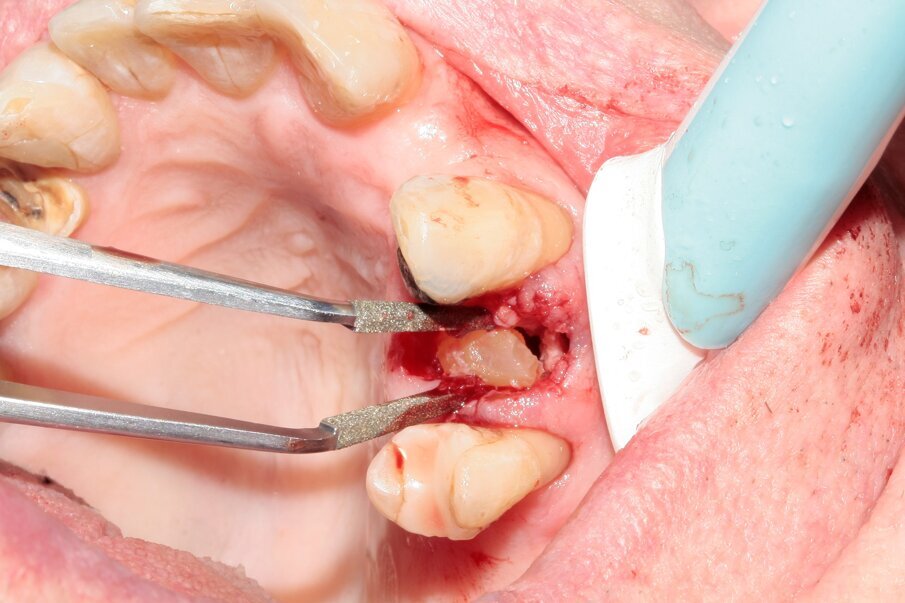

Figs. 5–7: Luxation was continued with Luxator P1 (straight blade, dark green).

Fig. 8: The tooth was removed with the help of diamond tweezers.